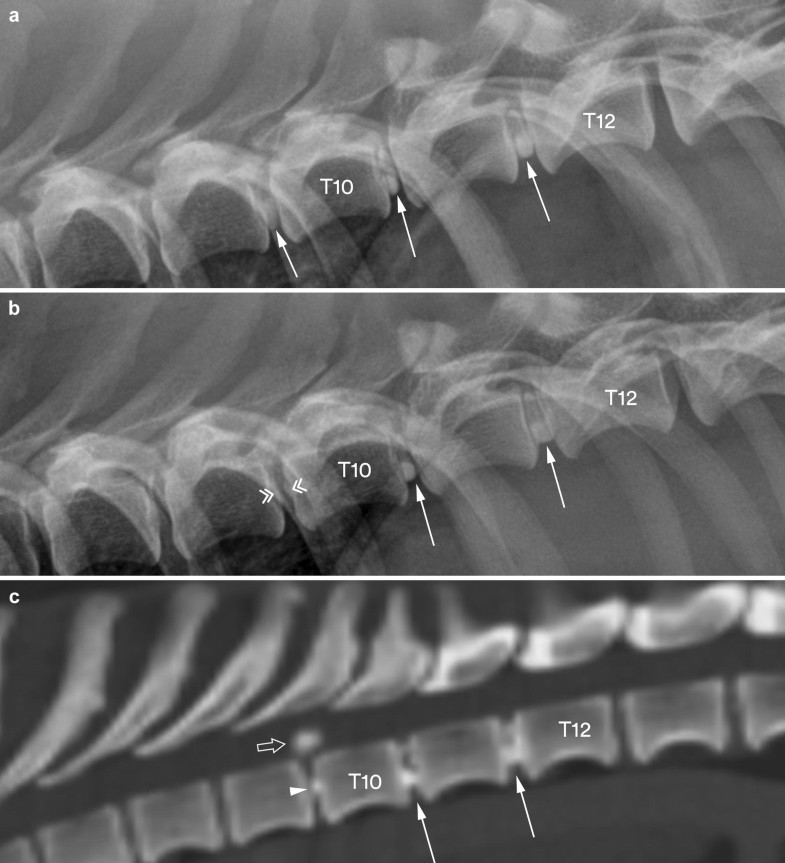

From www.researchgate.net

From www.frontiersin.org